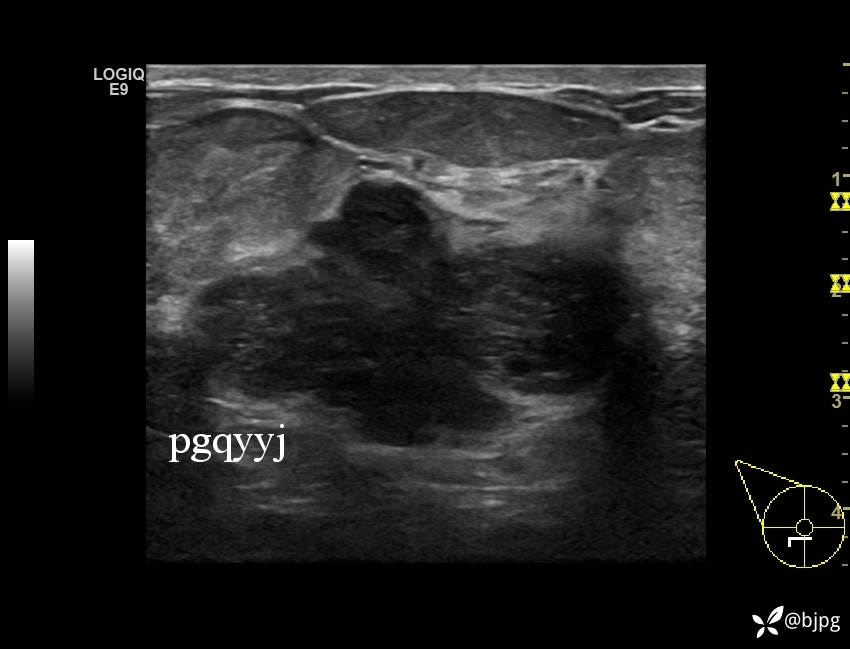

【患者信息】:女性36岁

【主诉】:发现右乳肿物一周

【检查】:超声

【临床诊断】:右乳结节,性质待定

【治疗经过及结果】:穿刺活检,欢迎同道讨论,穿刺病理数日后公布。

乳腺分叶状肿瘤 (7)